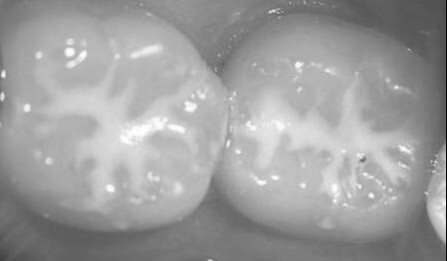

Ez a kezelés egy megelőző céllal segíti a gyermekek rágófogainak mély barázdáinak védelmét.

Gyermekeknél a fogszuvasodások 60-80%-a a rágófelszíni barázdákban és gödröcskékben kezdődik, ezek képezik a fogak legsérülékenyebb területeit. A barázdazárás éppen ezekre a veszélyeztetett területekre jelent foganyag kímélő hatékony megelőzési technikát.

A fogszuvasodást a savas, cukros ételek-italok fogyasztása során visszamaradt baktériumok által termelt savak okozzák. Ezek a savak kioldják a fogzománcból a kálcium- és foszfátionokat. Amennyiben ez a folyamat megbomlik, illetve az elégtelen szájhigiéniának köszönhetően elszaporodik a savat termelő baktérium, úgy beszélhetünk fogszuvasodásról. Ez a fogzománc védő kezelés alkalmas gyermekek és felnőttek számára egyaránt.